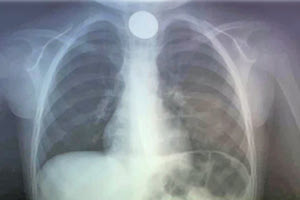

ΙΣΧΥΡΕΣ ΠΙΕΣΕΙΣ ΤΟΥ ΕΣΥ ΑΠΟ COVID, ΑΝΑΠΝΕΥΣΤΙΚΑ ΚΑΙ ΙΩΣΕΙΣ: Η μικρή εμβολιαστική κάλυψη γεμίζει νοσοκομεία και κλινικές